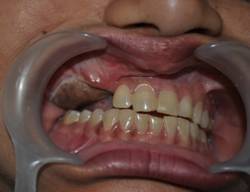

INTRA ORAL IMAGES

OCCLUSION REHABILITATION

BALANCED OCCLUSION REHABILITATION